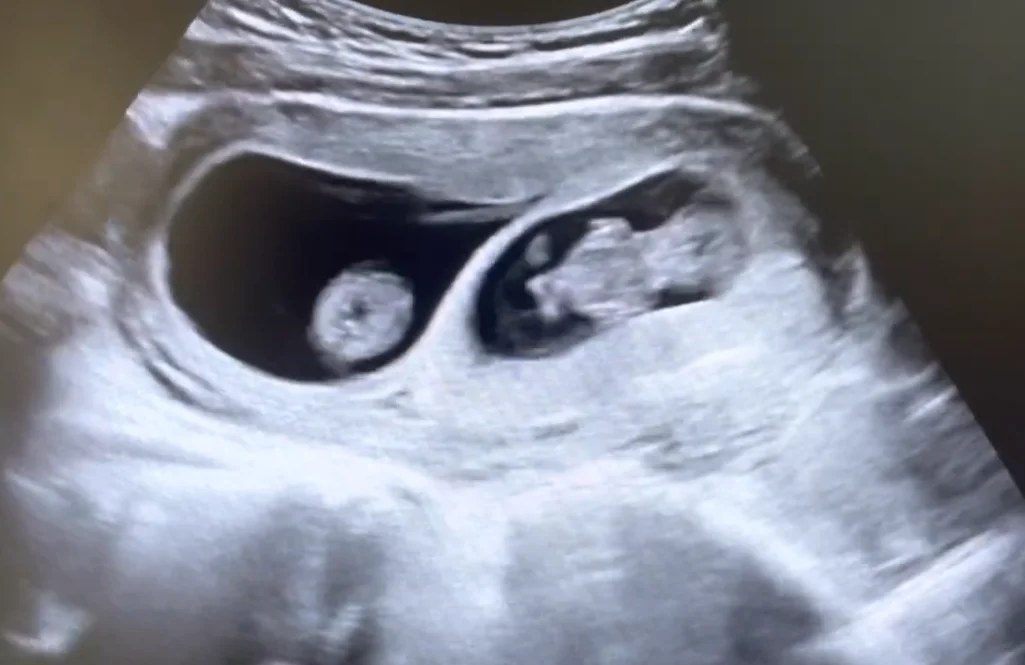

Song thai một nhau - hai ối (Monochorionic Diamniotic Twins - MCDA)